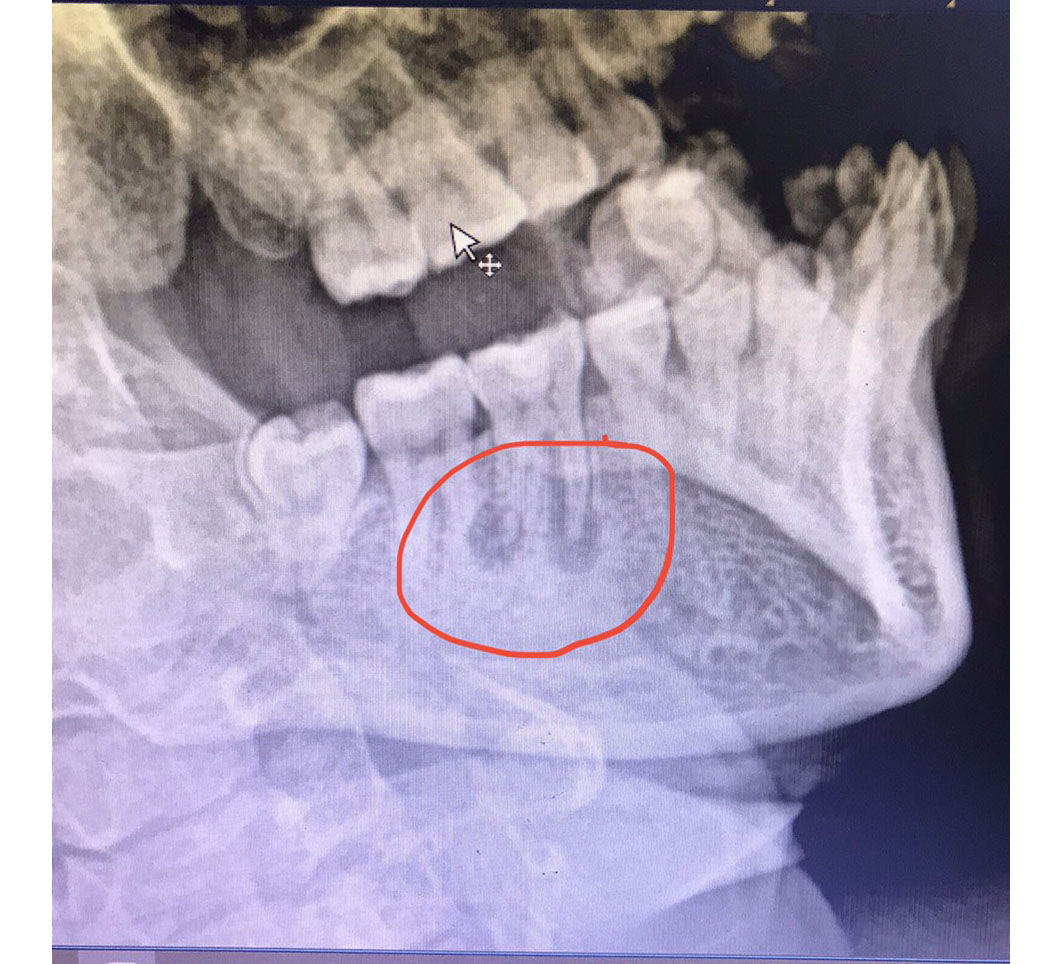

Hình ảnh X.Quang hàm chếch cho thấy hình ảnh nang xương hàm, có nhiều ổ dịch ở vị trí chân răng 3.6

Bệnh nhân Đ hay bị đau nhức quanh chân răng 3.6 nhiều năm nay, mấy ngày gần đây bệnh nhân đau nhiều kèm theo có mủ rò ra ở vị trí góc hàm dưới trái, BN vào viện khám và điều trị. Qua thăm khám, các BS thấy có mủ rò ra theo vị trí góc hàm dưới trái, ấn có khối xơ cứng. Hình ảnh X.Quang hàm chếch cho thấy hình ảnh nang xương hàm, có nhiều ổ dịch ở vị trí chân răng 3.6. Bn được chẩn đoán: Nang xương hàm và được thực hiện phẫu thuật cắt nang chân răng kết hợp huyết tương giàu tiểu cầu.